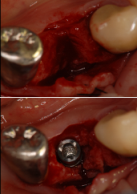

大口式インプラント

金曜日に大口式インプラント埋入法で右下4番にインプラントを入れました。CTでも予想していたのですが外側の骨がほとんどない状態で、通常の方法だとかなり難しい症例です。歯肉を開いてみると外側がほとんどなくなっていたのですが、後ろ側に少しボリュームがありました。そこで起始点をそこにもっていきどんどん広げていきました。途中硬かったので、ハイブリット法でドリルと併用しながらおこないました。最後にはご覧のとうり定位置に3.8mm×13mmのcamlogインプラントがうまく入りました。通常の方法ですと、外側にかなり人工の骨を造骨しなければならないケースです。それでも骨ができるか疑問です。来週はこの大口式の講演で大阪に行ってきます。